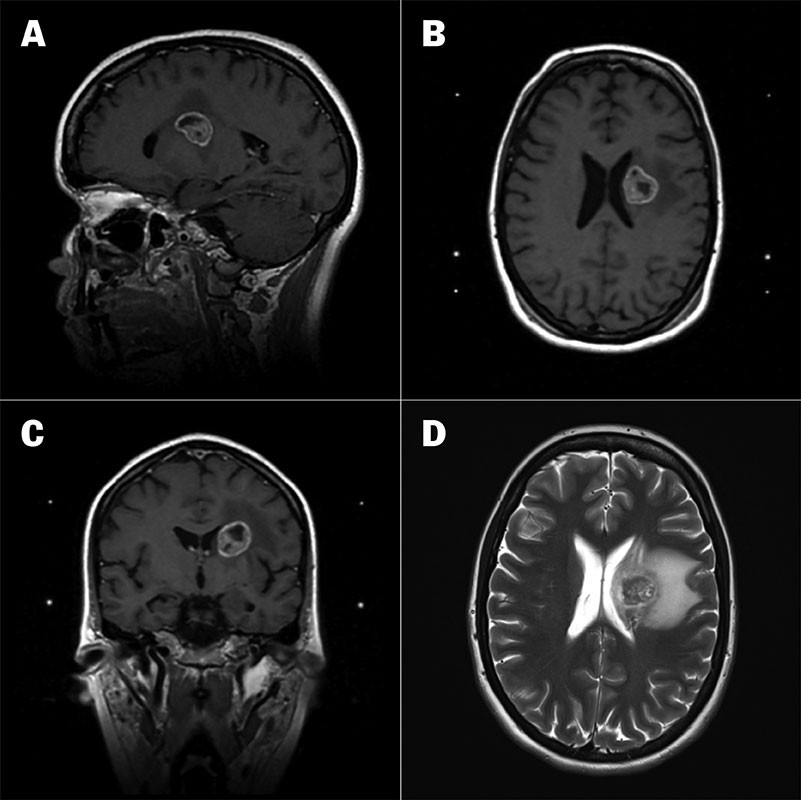

CT- og MR-undersøkelser av hodet avdekket en 23 mm stor ekspansiv prosess med omgivende ødem i venstre talamus som utøvet masseffekt på tilstøtende venstre sideventrikkel (figur 1a–d). CT-undersøkelse av brysthulen avdekket en 5,6 cm stor svulst i høyre lunges overlapp (figur 2). Det forelå forstørrede lymfeknuter paratrakealt på høyre side (stasjon 4R) og paraaortalt (stasjon 6R).

Man mistenkte nå lungekreft med spredning til lymfeknuter og hjerne. Finnålsaspirasjonscytologi etter bronkoskopisk prøvetaking fra lymfeknute 4R viste metastase fra lavt differensiert ikke-småcellet karsinom og bekreftet diagnosen.